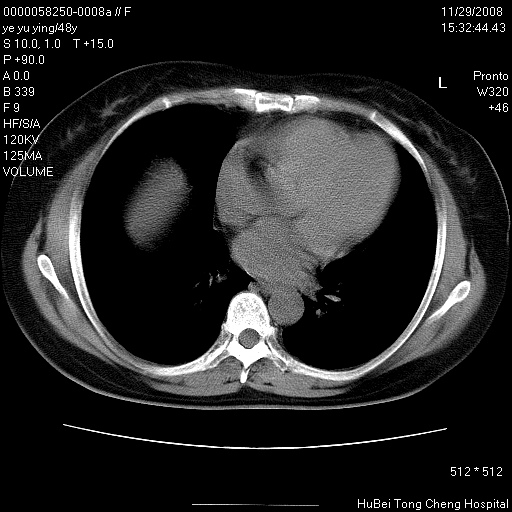

以下是引用zsl6918在2008-11-29 21:47:00的发言:[br]恶性肿瘤病史,转移瘤首先考虑。脂肪肝,胆囊结石。

以下是引用huenhao在2008-11-29 22:11:00的发言:[br]脂肪肝,胆囊结石。左肺病灶建议定期复查。

以下是引用liuyue在2008-11-30 5:44:00的发言:[br]1.左肺病变,首先考虑感染性病变,转移待排;建议治疗后复查。[br]2.肝脏密度普遍减低,考虑与化疗有关。[br]3.胆囊结石.